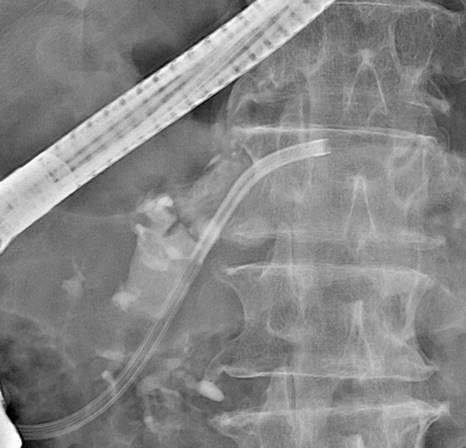

肝門部領域胆管癌の術後に胆管空腸吻合部に再発を認めた症例です。

本症例はRoux-en-Y再建後であり、ダブルバルーン内視鏡を用いて胆管まで到達しました。胆管造影を行い、狭窄部を確認した後、前区域枝に2本、後区域枝に1本、合計3本のステントを留置しました。

左上:Roux-en-Y再建後でした。ダブルバルーン内視鏡を用いました。

右上:到達後、胆管造影を行い、狭窄部の確認をしました。

左下・右下:前区域枝に2本・後区域枝に1本のステントを留置しました。